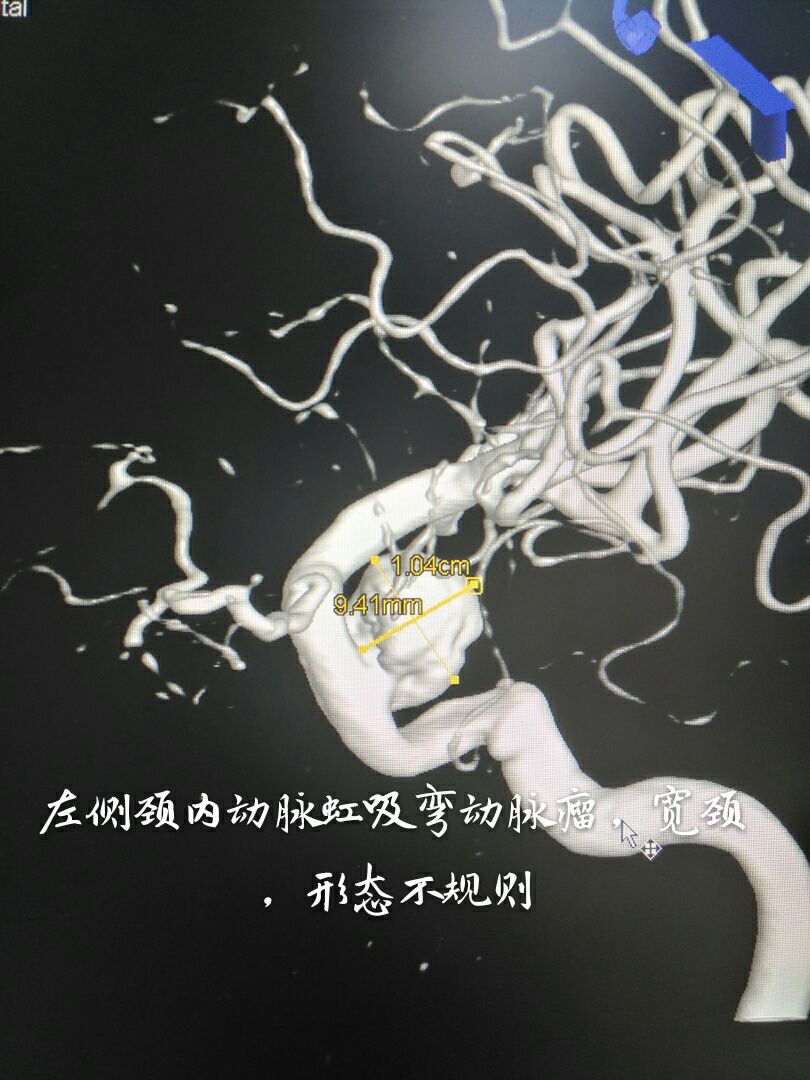

病例一:左侧颈内动脉虹吸弯大动脉瘤,宽颈,形态不规则

支架辅助+双微导管技术致密栓塞动脉瘤